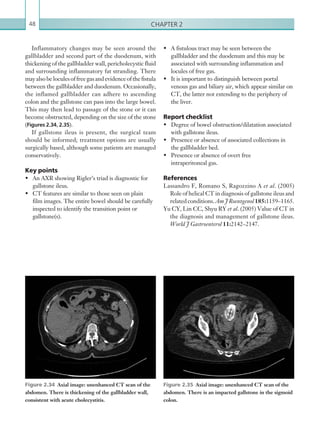

radiology opinion.

(a) (b)

K22247_C001.indd 9 16/05/15 3:06 AM

Chapter 110

PULMONARY EMBOLISM

Pulmonaryembolismisamedicalemergency,although

clinical presentation varies according to the degree of

arterial occlusion. Pulmonary emboli most commonly